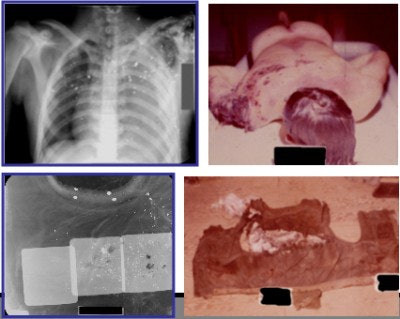

| An example of a pattern II mine injury. Two radiographs of a typical pattern II mine injury with extensive shrapnel fragments in the chest and abdomen and of the compromised body armor (flak vest). The corresponding photographs of the casualty and the flack vest are shown. Caption courtesy of Drs. Justin Dodge and James Smirniotopoulos, photos and radiographs from the WDMET archive. |

- Pattern II results from fragmentation mines, which explode at waist height, have a killing zone of 25 meters (80 feet), and have an injury zone of 200 meters (656 feet). Injuries occur to the head, neck, chest, or abdomen and are often fatal.